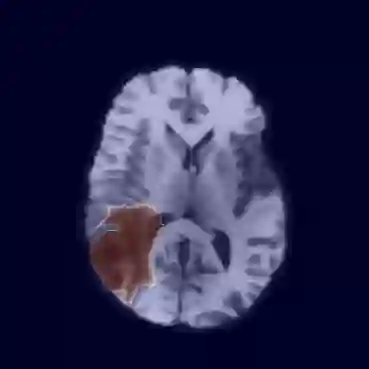

Unsupervised Anomaly Detection has become a popular method to detect pathologies in medical images as it does not require supervision or labels for training. Most commonly, the anomaly detection model generates a "normal" version of an input image, and the pixel-wise $l^p$-difference of the two is used to localize anomalies. However, large residuals often occur due to imperfect reconstruction of the complex anatomical structures present in most medical images. This method also fails to detect anomalies that are not characterized by large intensity differences to the surrounding tissue. We propose to tackle this problem using a feature-mapping function that transforms the input intensity images into a space with multiple channels where anomalies can be detected along different discriminative feature maps extracted from the original image. We then train an Autoencoder model in this space using structural similarity loss that does not only consider differences in intensity but also in contrast and structure. Our method significantly increases performance on two medical data sets for brain MRI. Code and experiments are available at https://github.com/FeliMe/feature-autoencoder

翻译:通常,异常检测模型产生输入图像的“正常”版本,而两者的像素-WY $l ⁇ p$-difference被用来将异常现象本地化。然而,由于大多数医学图像中存在的复杂的解剖结构的重建不完善,大量残留物往往出现。这种方法也未能检测出与周围组织没有严重强度差异特征的异常现象。我们提议使用地貌图功能来解决这个问题,将输入强度图像转换成一个有多种频道的空间,在从原始图像中提取的不同歧视性特征地图中可以检测出异常现象。我们然后在这个空间中培训一个自动编码模型,使用的结构相似性损失不仅考虑到强度差异,而且还考虑到对比和结构。我们的方法大大提高了大脑MRI两个医学数据集的性能。我们的方法和实验可在 https://github.com/FeliME/featriat-autoencoder 上查阅。